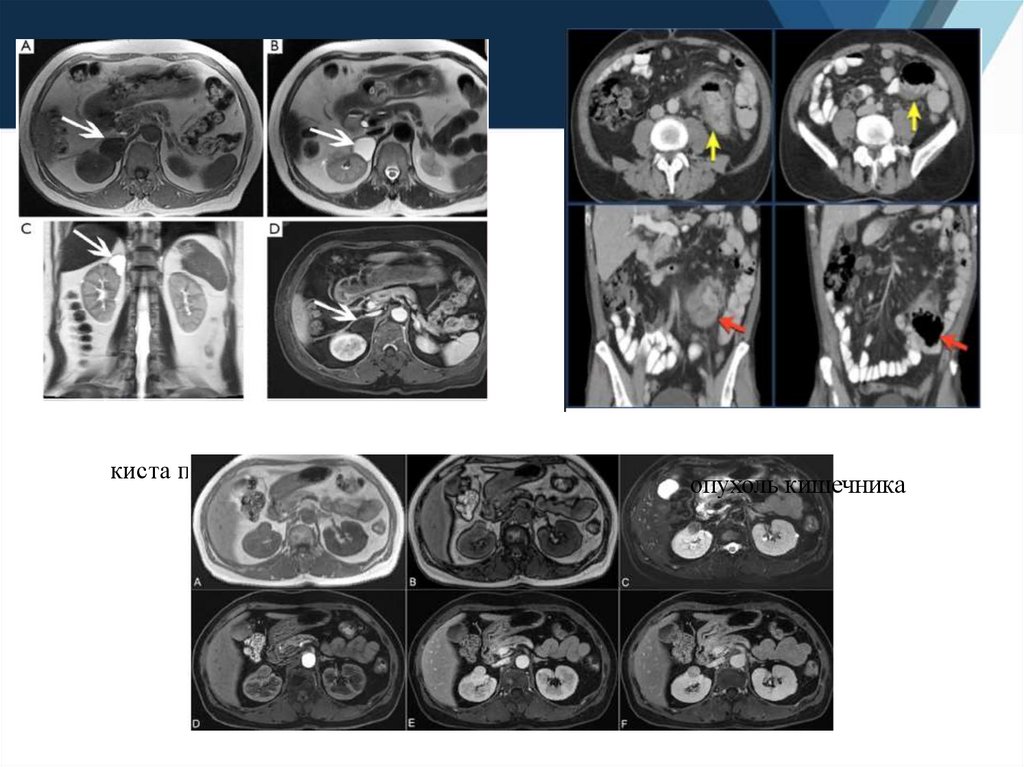

киста правого надпочечника

опухоль кишечника